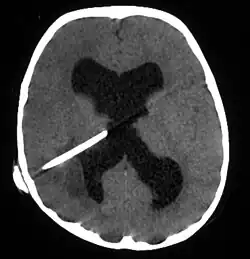

The diagnosis is established by a computed tomography (CT) (with contrast) examination. At the initial phase of the inflammation (which is referred to as cerebritis), the immature lesion does not have a capsule and it may be difficult to distinguish it from other space-occupying lesions or infarcts of the brain. Within 4–5 days the inflammation and the concomitant dead brain tissue are surrounded with a capsule, which gives the lesion the famous ring-enhancing lesion appearance on CT examination with contrast (since intravenously applied contrast material can not pass through the capsule, it is collected around the lesion and looks as a ring surrounding the relatively dark lesion). Lumbar puncture procedure, which is performed in many infectious disorders of the central nervous system is contraindicated in this condition (as it is in all space-occupying lesions of the brain) because removing a certain portion of the cerebrospinal fluid may alter the concrete intracranial pressure balances and causes the brain tissue to move across structures within the skull (brain herniation).[14]

CT guided stereotactic aspiration is also indicated in the treatment of brain abscess. The use of pre-operative imaging, intervention with post-operative clinical and biochemical monitoring used to manage brain abscesses today dates back to the Pennybacker system pioneered by Somerset, Kentucky-born neurosurgeon Joseph Buford Pennybacker, director of the neurosurgery department of the Radcliffe Infirmary, Oxford from 1952 to 1971. [19]